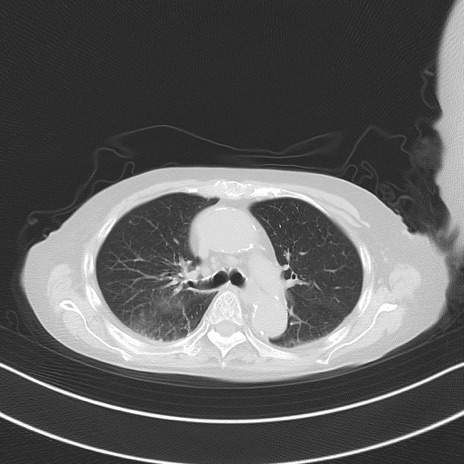

横断像

冠状断像